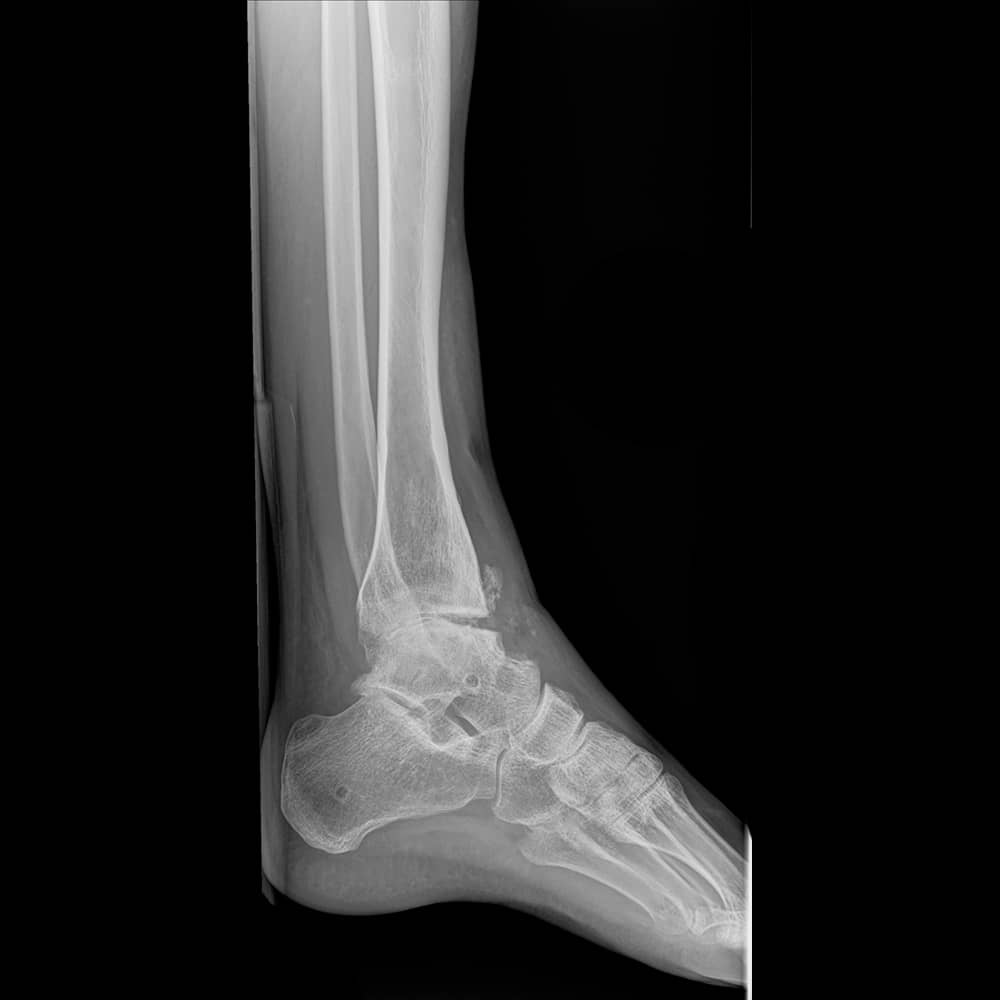

Ankle with near fusion

Each fusion requires stripping away the remaining cartilage covering the bones, then screwing together the bones to compress them while the body heals by adhering one raw bone to another. Here are a few examples of joint degradation and thoughts about how we might approach them in the near future.